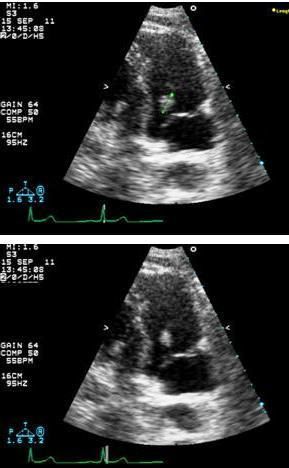

An echocardiogram revealed a 1.3-cm mobile mass attached to the tricuspid valve (Figure, green line, top image). The differential diagnosis included clot in transit, cardiac tumor, and cardiac vegetation.

A cardiac surgeon was consulted and recommended resection of the valvular mass. During the resection, cardiac catheterization showed normal coronary vasculature. Histologic examination confirmed the mass to be a benign papillary fibroelastoma (PFE). The patient was discharged home and a follow-up echocardiogram showed resolution of the mass with no evidence of valvular dysfunction.